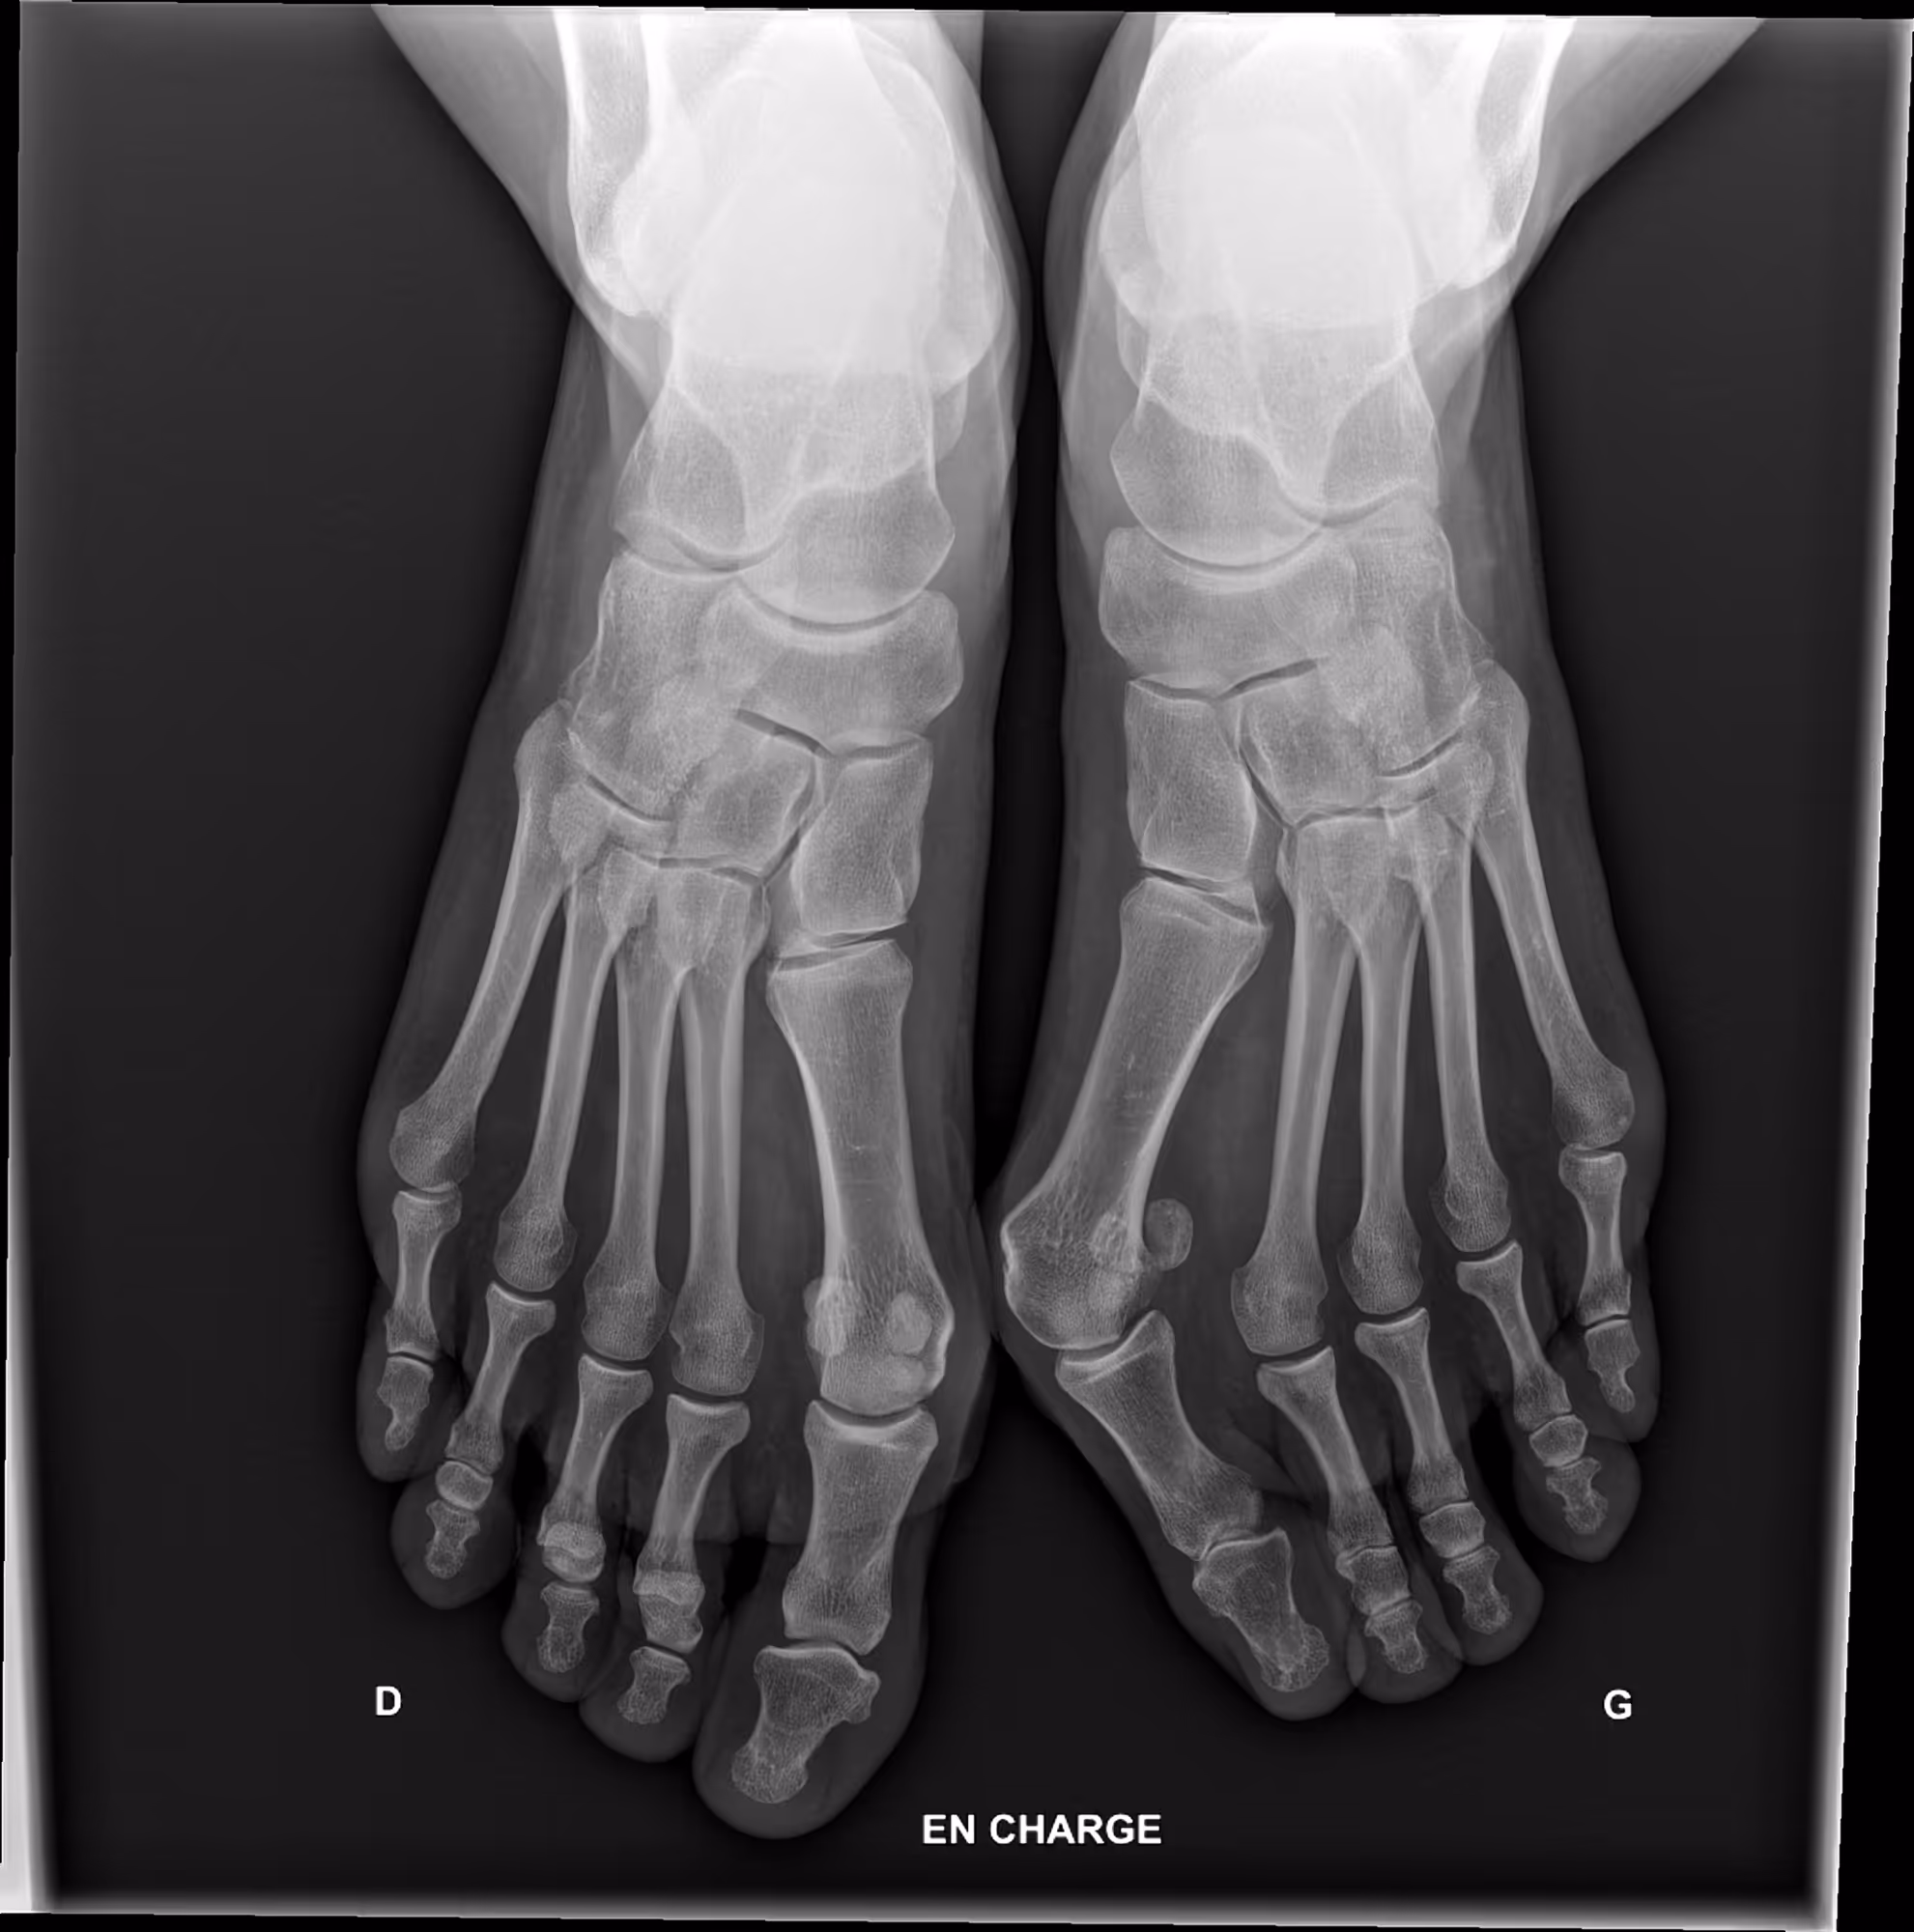

Indication

This is the defA 45-year-old female presenting with foot discomfort and difficulty wearing shoes.ault title value

Results

BoneMetrics detected a bilateral hallux valgus, with greater deformity on the left side.

Hallux valgus angle

1st-2nd intermetatarsal angle

1st-5th intermetatarsal angle

Meary

Angle of the hind foot on Meary ring film